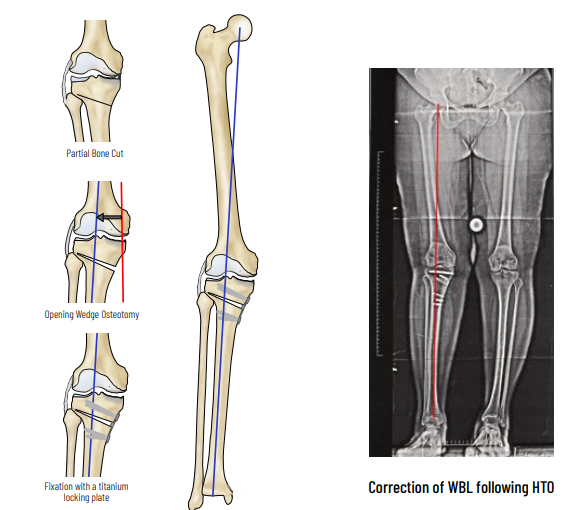

HTO - High Tibial Osteotomy

HTO is a procedure to correct the alignment and to distribute the load to the non-involved compartment. Arthroscopy is done to assess the status of the joint and to treat meniscal tears, loose bodies & cartilage tears. Based on preoperative planning and using precision instrumentation, a partial bone cut (osteotomy) is made in the upper tibia and is slowly opened to the desired level to shift the load to the normal compartment.